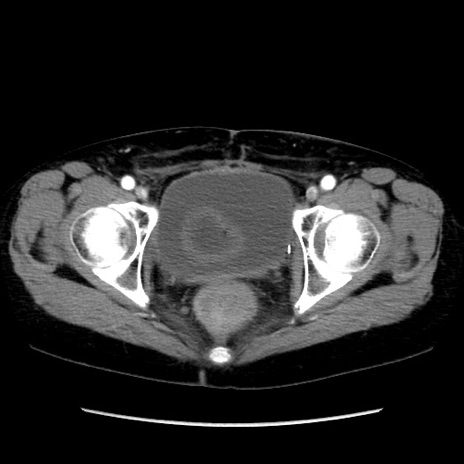

症例32(横断像)

【症例】40歳代 女性

【既往歴】子宮頚癌(広汎子宮全摘術、放射線療法)、腸閉塞

【身体所見】腹部:平坦、軟、腸雑音亢進、上腹部を中心に腹部全体に圧痛あり。

【データ】WBC 8400、CRP 0.03